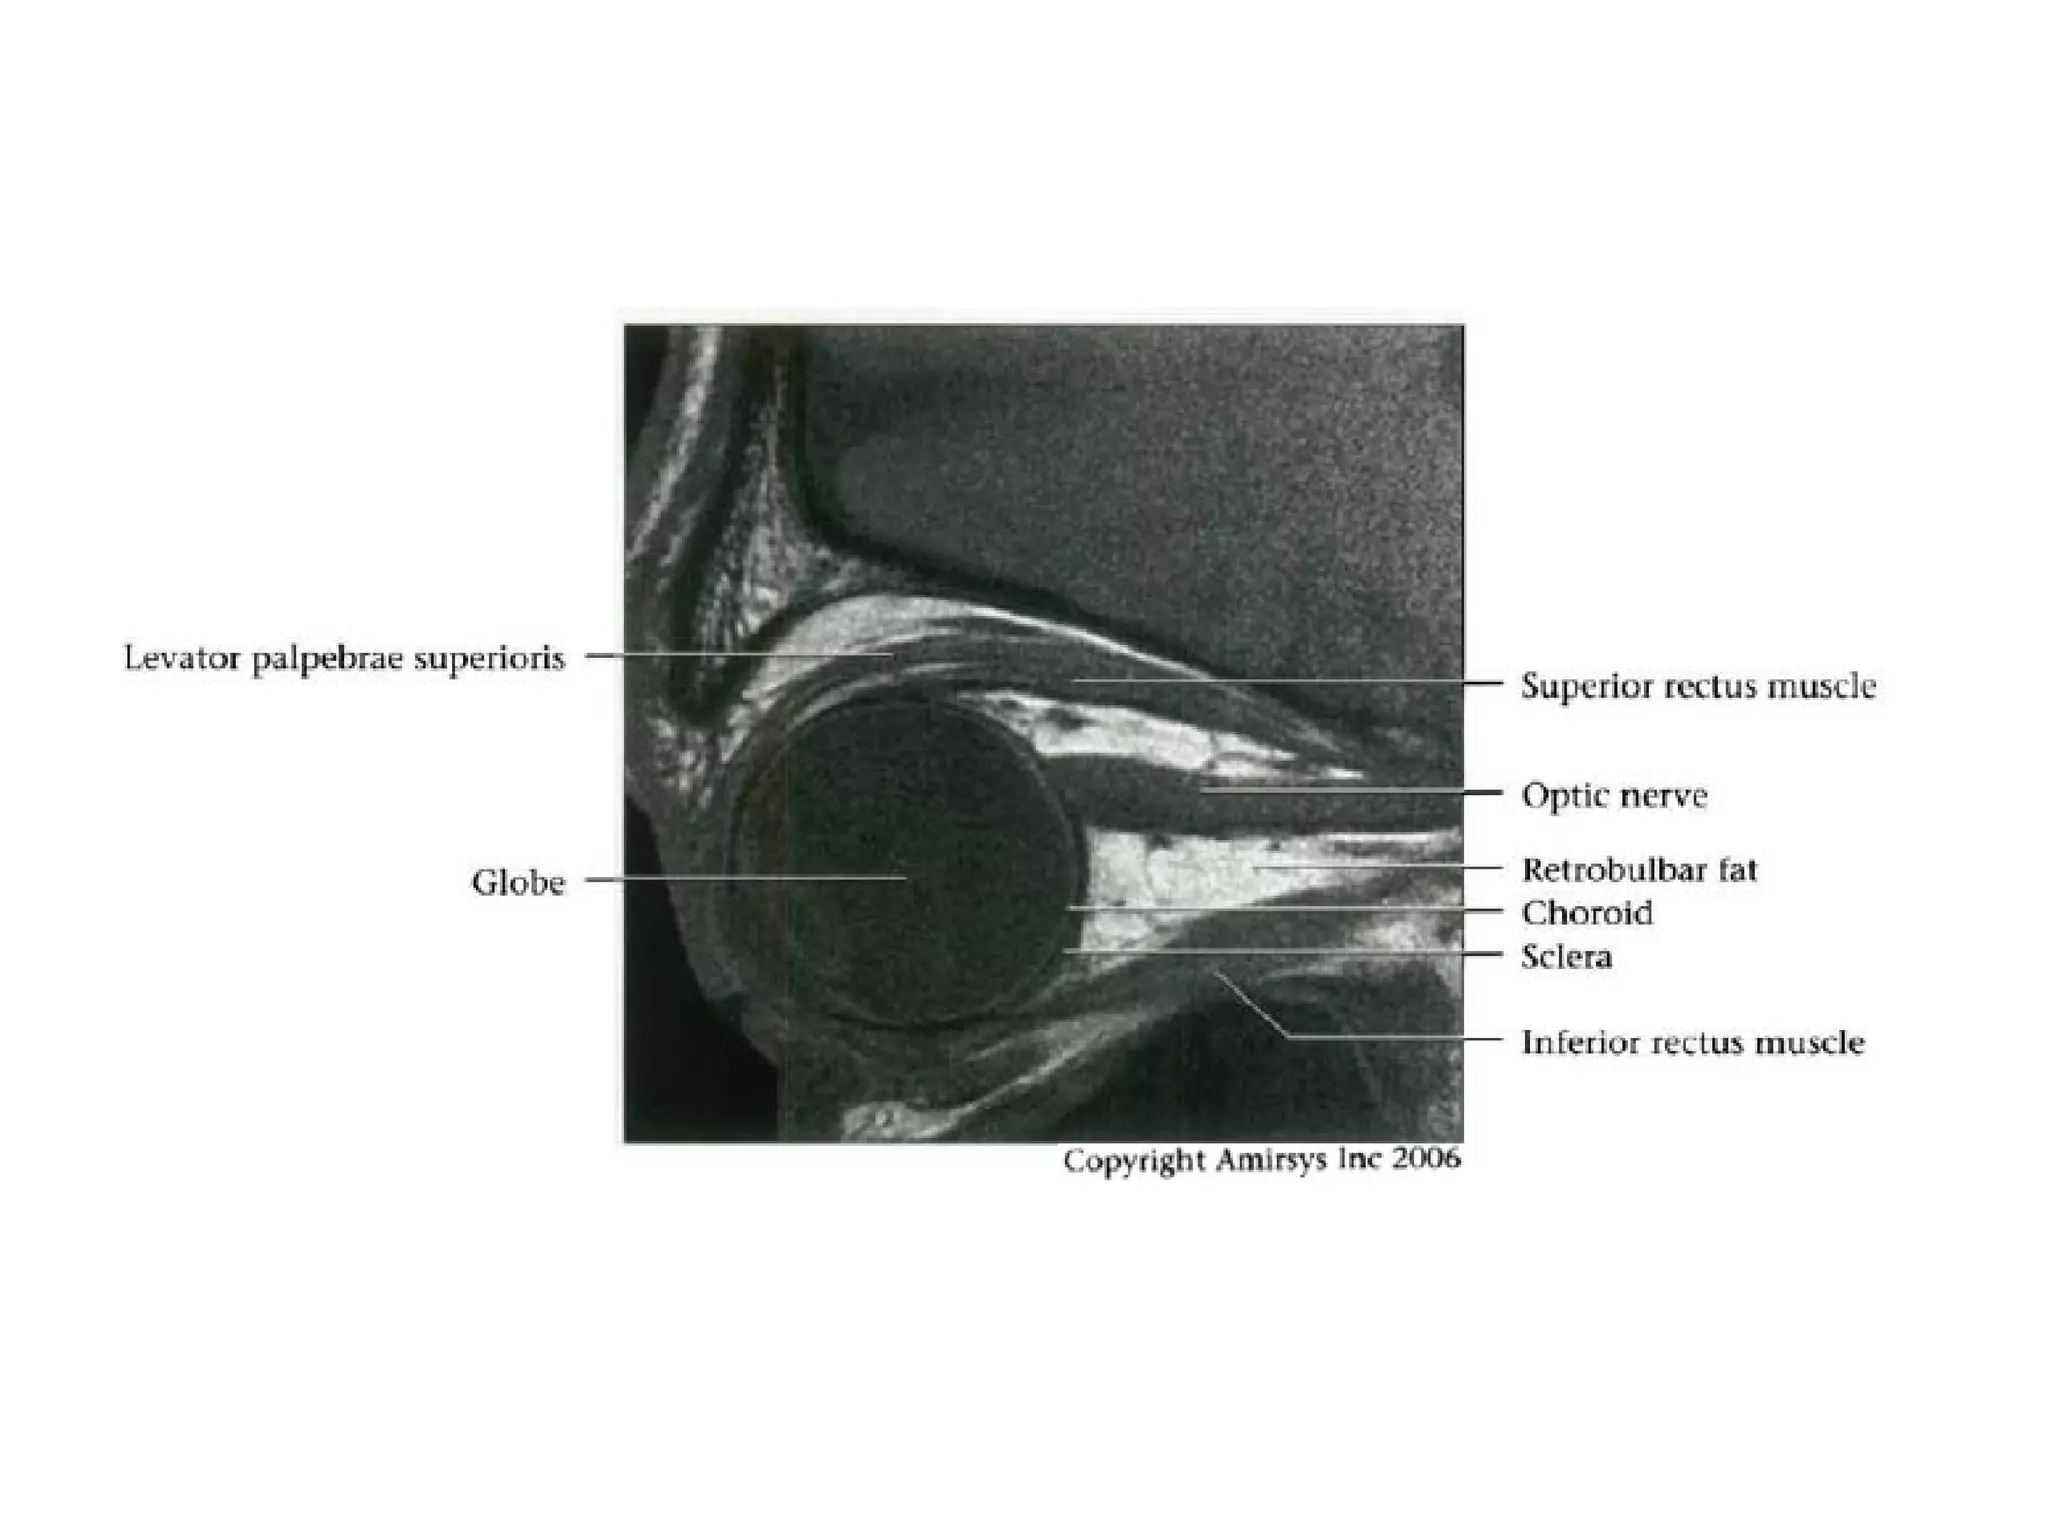

Intraocular segment

• 1 mm length

• Region of sclera termed lamina cribrosa

where ganglion cell axons exit globe

Intraorbital segment

• 20-30 mm in length

• Extends posteromedially from back of globe to orbital apex within

intraconal space of orbit

• CN2 longer than actual distance from optic chiasm to globe allowing

for movements of eye

• Covered by same 3 meningeal layers as brain

- Outer dura, middle arachnoid and inner pia

- Subarachnoid space (SAS) between arachnoid and pia contains

cerebrospinal fluid (CSF); continuous with SAS of suprasellar

cistern

- Fluctuations in intracranial pressure transmitted via SAS of optic

nerve-sheath complex

• Central retinal artery

- 1st branch of ophthalmic artery

- Enters optic nerve about 1 em posterior to globe with

accompanying vein to run to retina

Cranial Nerve II:

The Optic Nerve

• Like the olfactory nerve, the optic nerve is a white-matter tract

without surrounding Schwann cells.

• It includes four anatomic segments: retinal, orbital, canalicular,

and cisternal.

• The retinal segment leaves the ocular globe through the lamina

cribrosa sclerae (the optic foramen of the sclera).

• The orbital segment, which is surrounded by a dural sheath

containing CSF, travels through the center of the fat-filled orbit.

• The canalicular segment is the portion that lies in the optic canal,

below the ophthalmic artery. This segment of the nerve is frequently

overlooked on radiologic images, so it should be specifically sought

when imaging for vision loss.

• Finally, the cisternal segment of the nerve can be visualized in the

suprasellar cistern, where the nerve leads to the optic chiasm. The

anterior cerebral artery passes over the superolateral aspect of the

cisternal segment of the nerve.

RadioGraphics 2009; 29:1045–1055